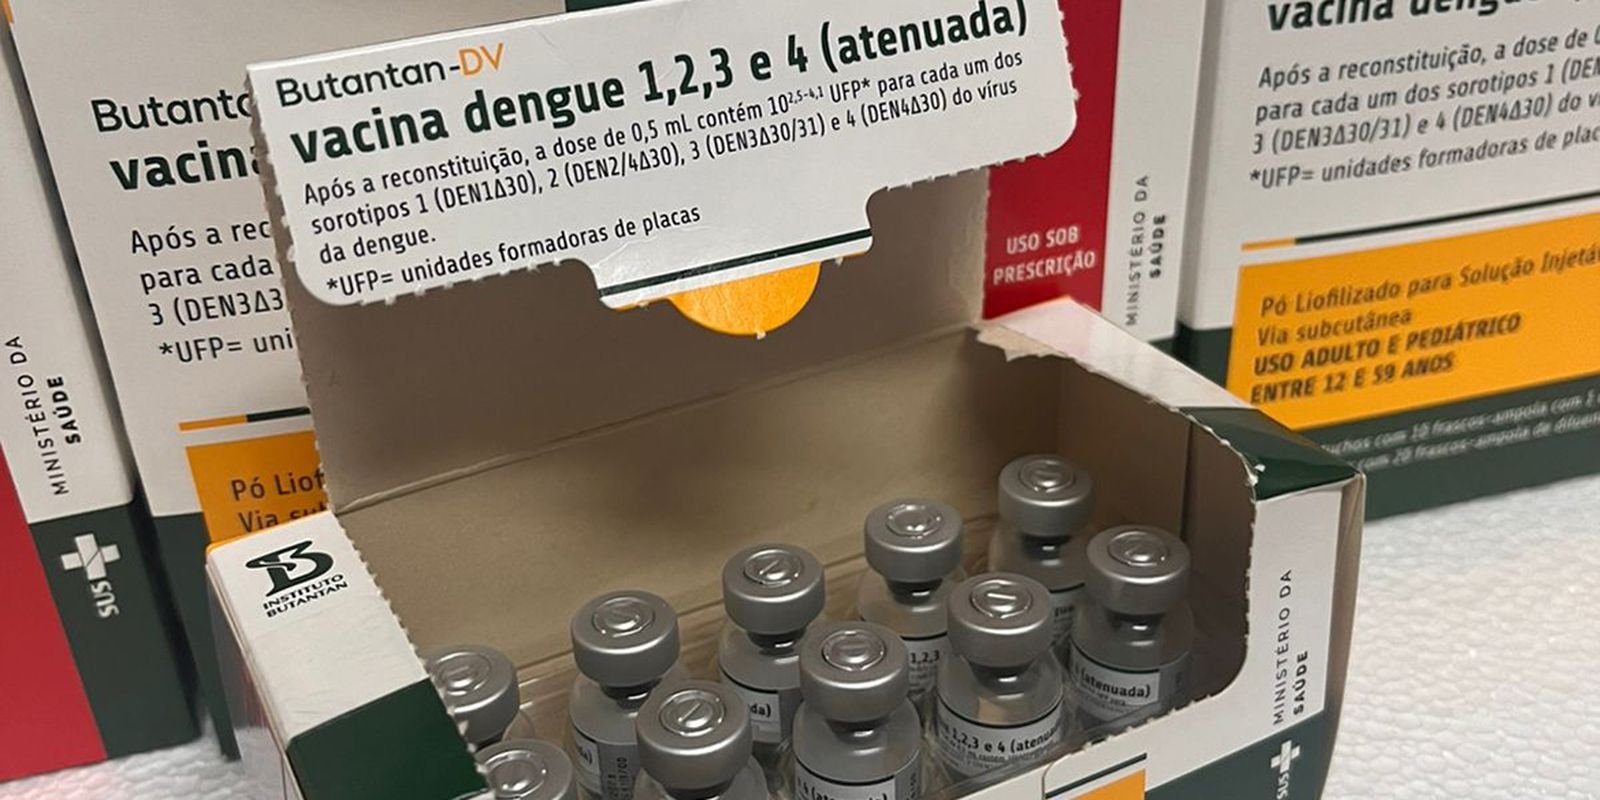

Segundo o diretor da Organização Pan-Americana da Saúde (OPAS) – (braço da OMS), Jarbas Barbosa, em 2024, as Américas registraram mais de 13 milhões de casos de dengue com mais de 8,4 mil mortes.

“A dengue não é mais apenas uma doença tropical, mas um forte indicador global da relação entre mudança climática e as arboviroses provando que a saúde humana não pode ser separada da saúde do meio ambiente e dos sistemas em que se vive”, diz.

De acordo com o diretor da Opas, as Nações Unidas tem atuado de forma regional nas Américas com o objetivo de antecipar riscos e integrar a vigilância entre os países, viabilizando o acesso a vacinas por meio do Fundos Rotativos Regionais.